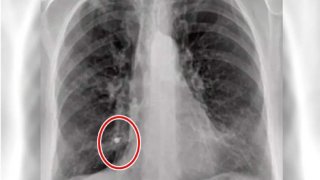

หมอโชว์ฟิล์มปอด ของผู้ป่วยโควิดวัย 80

เมื่อวันที่ 28 ก.ค. 2564 นายแพทย์ "โยธิน วิเชษฐวิชัย" แพทย์ชำนาญการด้านจิตเวช โรงพยาบาลสมิติเวช ได้โพสต์ภาพฟิล์มเอกซ์เรย์ปอด ของคนไข้โควิด วัย 80 ปี พร้อมระบุข้อความว่า ดูเพิ่ม